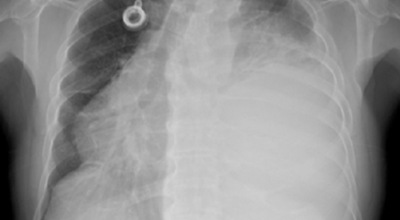

폐암 검사는 X-ray를 통해서 검사하는데 , 크기가 작거나 구석에 위치한 경우 확인이 어려운 경우도 있답니다. 그리고 조직 검사를 통해서 정확한 진단을 하게 되어요. 폐암이 발견되면 종양의 크기나 전이 여부 , 위치에 따라서 수술 여부를 결정하게 되어요.